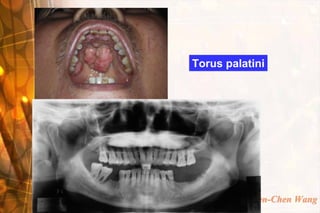

Torus palatini

Wen-Chen Wang

Consistency  Fluctuation & emptiability: Fluid contented lesion  Soft: vein, loose CT, glandular tissue  Cheesy: sebaceous cyst, epidermoid cyst  Rubbery: relaxed muscle, glandular tissue with capsule, arteries  Firm: fibrous tissue, tensed muscle, large nerve  Bony hard: bone, cartilage, tooth structure Wen-Chen Wang

• 33.

Torus palatini Wen-Chen Wang